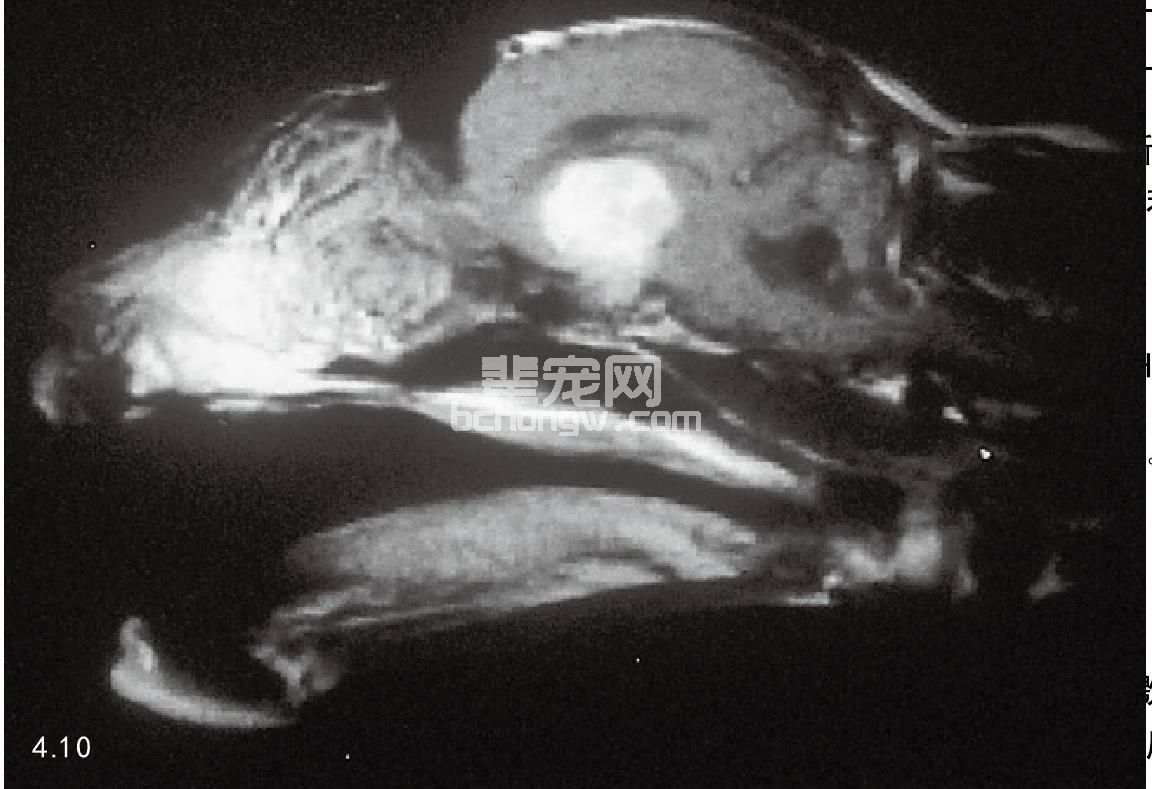

诊断 在很多病例,实验室诊断发现糖尿病失去控制,多数病例表现高血糖症和糖尿,通过检测血清GH和 IGF-1浓度可以确诊肢端肥大症(图4.10)。

这种病例要对头盖骨做CT和MRI检查显示垂体肿瘤的大小和位置。

图4.10 肢端肥大症家养短毛患猫,脑部电磁波图像发现有垂体肿瘤。